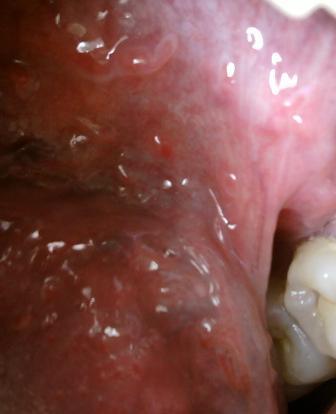

尖锐湿疣会复发吗尖锐湿疣病毒不仅是比较顽固的,而且也是会复发,疾病一般在治愈之后的三个月左右的时间是疾病复发的高峰期,因此为了降低疾病复发的几率,在积极进行治疗的同时,必要的护理工作也是不可以少的。不同患者病情的差异,因此在选择治疗方法的时候也应该区别对待。